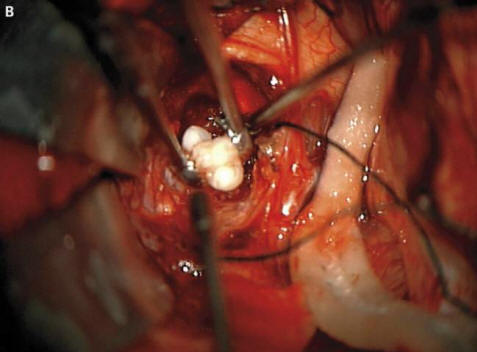

valokuva avoimista lähteistä Kuten kirurgit selittivät pelättyjä vanhempia ja onkologit, tämä johtui harvinaisen synnynnäisen muodostumisesta kasvaimet – craniopharyngiomas, kirjoittaa New England Journal of Medicine. Tämä kasvain valtaosassa tapauksia hyvänlaatuinen voi kuitenkin kasvaa pallon palloksi golf ja aiheuttaa hajua heikentyneen kuulon ja näkökyvyn heikkenemisen, ja lisää myös kallonsisäistä painetta. Tutkijat aina epäili, että nämä kasvaimet, jotka ilmenevät lapsessa jo raskaus, muodostettu samoista soluista kuin hampaat, koska ne havaitsivat suuria kalsiumkerroksia, mutta todellisen muodostuneen hampaan ennen tätä tapausta, jota he eivät löydä kirjanpito

Kirurgit poistivat kuvan onnistuneesti avoimista lähteistä poika, he sanoivat, menee hyvin. Kuitenkin hammas että kasvoi aivolisäkkeessä, mutta häiritsi erityisesti aivoja, asianmukainen hormonien tuotanto – potilaan on otettava ne ennen elämän loppu. Tämä tapaus voi perustellusti olla ylpeä paikasta luettelo onkologien omituimmista toimenpiteistä. Sillä välin, vuonna nuori mies Iranista, joka piti hoita karvaiset silmät. Oudokas kasvain hänen silmässään ilmestyi melkein heti syntymän jälkeen, mutta 19 – vuotiaana se kasvoi huomattavasti vuonna 2006 (enintään 0,6 cm) ja estävät silmäluomien sulkemisen lisäksi siitä jäykät hiukset alkoivat kasvaa. Lääkärit poistivat kasvaimen ja havaitsivat sen tämä on limbaalinen dermoidi – erittäin harvinainen, yleensä hyvänlaatuinen koulutus. Lääkäreiden mukaan siinä tapauksessa jos nuori mies veti edelleen lääkkeillä, hänen turvotuksensa ei vain voinut kasvattaa hiuksia, vaan myös alkaa hikoilla: ajan myötä kasvaimissa vastaavat rauhaset ilmestyvät usein.